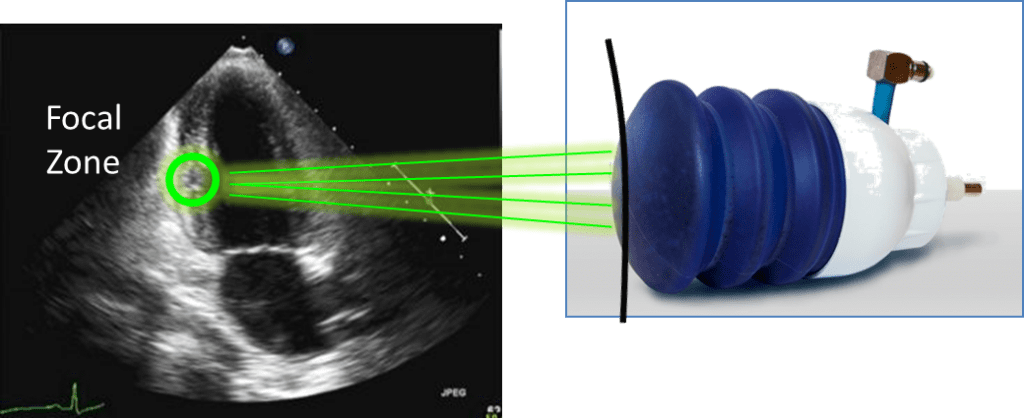

Principle

Low-energy focused shock waves (energy density 0.09 mJ/mm2)

Focused and controlled by echocardiography

Released by ECG trigger (during the refractory phase of the cardiac cycle)

Shock waves are a kind of sound waves (like ultrasound) with high intensity and short duration. The sound waves are generated by an underwater high voltage spark, which are delivered noninvasively, focused by a special ellipsoid reflector. The reflector is coupled to the patient’s skin near the affected area with a water cushion. The focal zonedistance into the patient’s body is adjusted according to the clinical requirements.

The treatment is performed using a shock wave generator that is designed to address the unique clinical-anatomical requirements of the chest cavity. A cardiac ultrasound imaging system is used to locate the treatment area and to map the exact position and extent of the ischemic zone. Shock waves are then delivered via the anatomicalacoustic window to the treatment area under E.C.G. R-wave gating. Several treatment sessions are required to obtain optimal results.